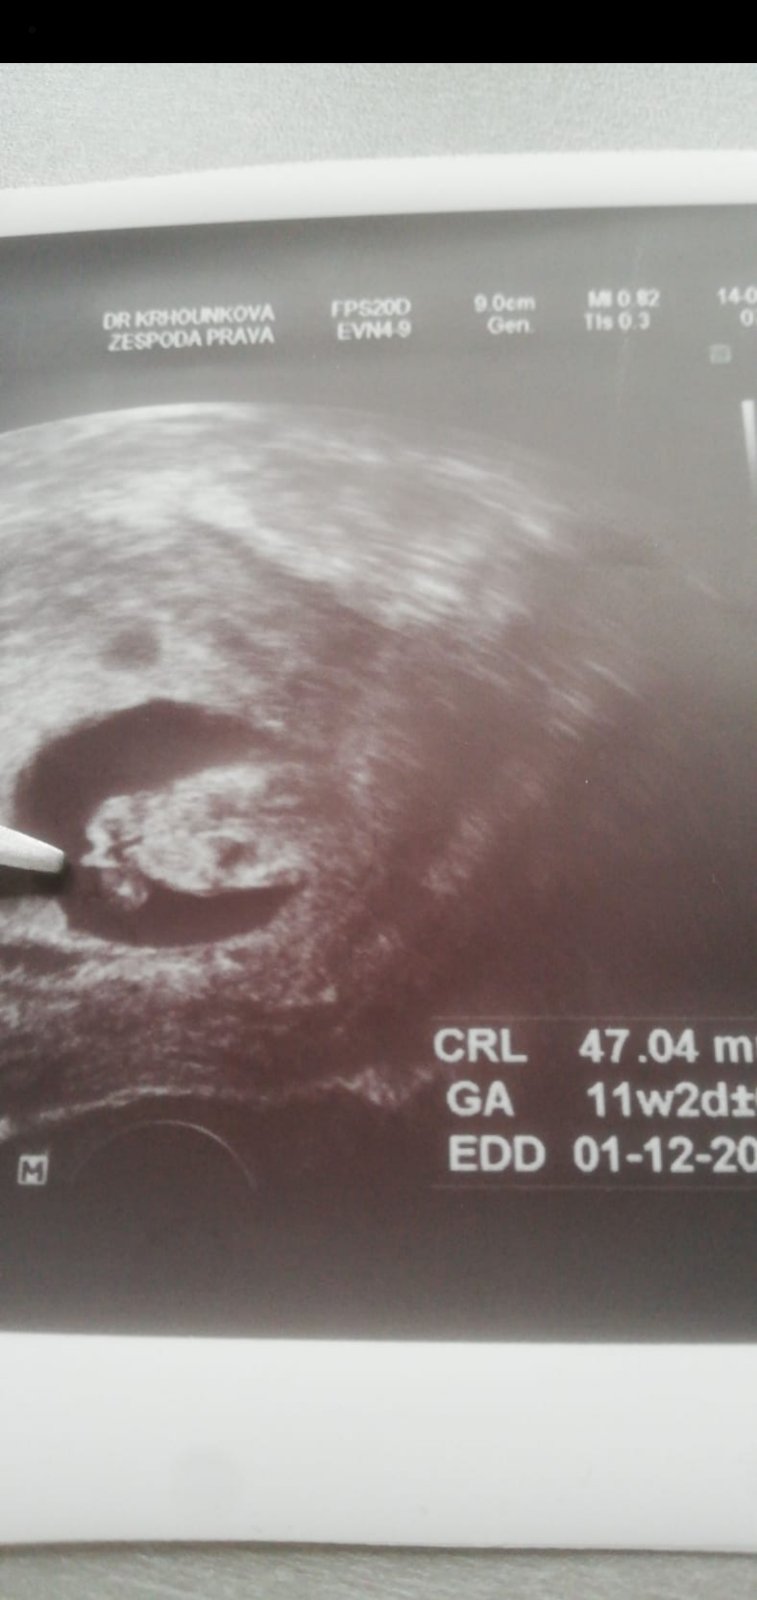

Ahoj, nepoznaly byste holky i tady?🙂